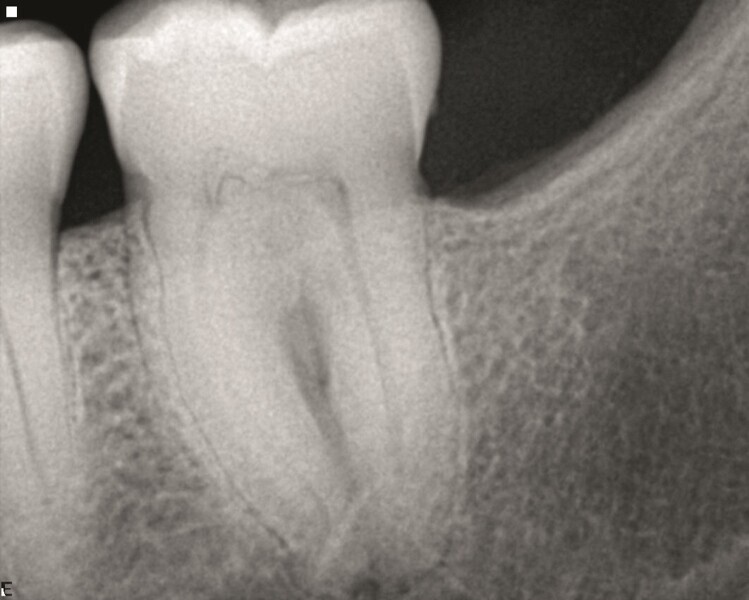

Cas 1

Ce patient m’a consulté en urgence pour une douleur aiguë affectant une deuxième molaire supérieure. Après un examen clinique confirmatoire, une radiographie standard (Fig. 1) a révélé une anatomie très complexe et une calcification pulpaire.

Selon la déclaration du patient, cette dent avait été restaurée par un inlay, mais une douleur était apparue au bout d’un certain temps, et avait persisté plusieurs années sans qu’aucun traitement ne soit proposé. Lors d’un examen de contrôle, le praticien lui avait dit que tout allait très bien.